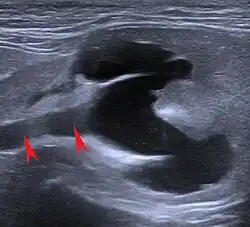

The main symptoms of chronic kidney disease in cats are lack of appetite (anorexia), increased drinking (polydipsia), increased urine output (polyuria), fatigue (apathy), vomiting and weight loss. In addition, diarrhea, inflammation of the oral mucosa (stomatitis) with the formation of ulcers (ulcera), increased salivation (hypersalivation) and bad breath may occur as a result of uremia. Increased blood pressure (arterial hypertension) with damage to the eye (fundus hypertonicus, hypertensive retinopathy), anemia (anemia), itching, dehydration, soft tissue calcifications, bleedings and accumulation of water in the tissues (oedemas) are also more frequent accompanying symptoms. In the case of severe uremia, neurological neurology manifestations such as apathy, seizures, delirium, coma, abnormal movements and muscle disorders (myopathys).[10] Typically, the symptoms—in contrast to acute renal failure—occur gradually over weeks, months or even years, and the general condition is poor. In addition, acute kidney failure is initially characterized by reduced urine production. However, an existing mild or moderate chronic kidney disease is often suddenly worsened by an acute event ("exacerbation") and thus becomes conspicuous to the cat owner. This can be the case, for example, if one kidney has already become a non-functioning shrunken kidney due to urinary retention and the second suddenly swells acutely due to urinary retention (hydronephrosis) and is damaged ("large kidney-small kidney syndrome") or if hyperthyroidism is treated and the glomerular filtration rate is suddenly reduced as a result.[17]

Ultrasound image of hydronephrosis in a cat. The arrows point to the dilated ureter.